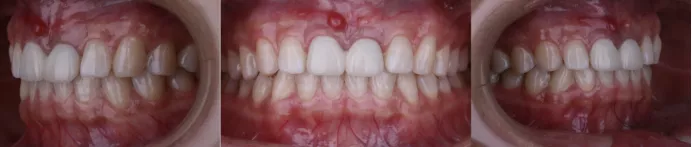

制作种植支持式临时修复体

·      植体植入三个月后,制作临时修复体,穿龈塑形。

定期检查,评估植体及牙龈情况

·     佩戴两个月后复查。

·     检查唇齿关系。

·     DSD。

修复体试戴及粘接

半年后复查